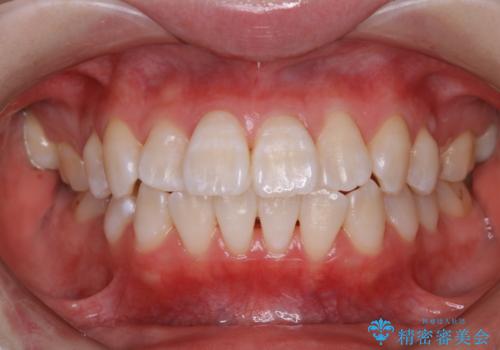

- マウスピース矯正中に、口臭が気になりクリーニングを行いたいとのことでした。染め出しをしての歯ブラシ指導とPMTC60分コースを行いました。

口腔内にはたくさんの細菌がいるため、ヌルヌルとしたプラーク(歯垢)が自然に歯の表面に付きます。

このプラーク(歯垢)にはたくさんの細菌が潜んでおり、虫歯や歯周病・口臭などの最大の原因です。そのため、毎日の歯磨きでプラーク(歯垢)をキレイに取り除くことが、健康な歯を保つためには欠かせません。

しかし、プラークは歯の色と似ているため、見ただけでは付着しているかどうかがハッキリとは分かりません。

染め出し液を使ってプラークを染め出すことにより、普段の歯みがきで磨き残している場所を目で確かめることができます。

日々の歯磨きを上達するには、まずどこが磨けていないか認識することが大切です。